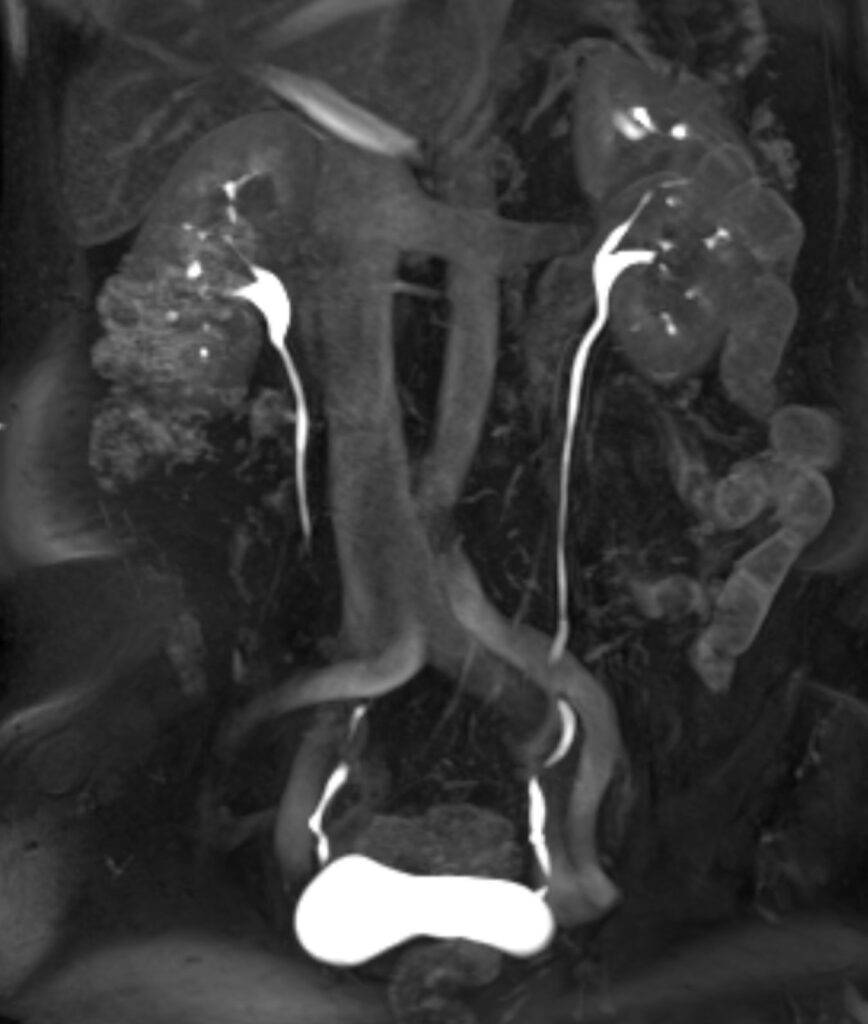

Was kann man auf einer MRT des Abdomens sehen?

Auf einer MRT-Aufnahme sind insbesondere die Organe im Bauchraum sichtbar, da Weichteile in einer MRT sehr gut abgebildet werden können.

Zu sehen und später im weiteren Verlauf beurteilbar sind:

- Leber, Gallengängen, Bauchspeicheldrüse, Nieren und Nebennieren mit Harnleiter, Milz, Becken

Durch die detailreichen Abbildungen können Veränderungen der Organe festgestellt werden, die auf bestimmte Krankheiten schließen lassen – so können beispielsweise Entzündungen oder Gewebsveränderungen im Bauchraum festgestellt werden.

Es kann zwischen gut- und bösartigen Tumoren unterschieden werden. Dies ermöglicht eine genaue Diagnose, woraufhin ein schnelles und geeignetes Therapieverfahren angesetzt werden kann.

Auch bei diffusen und nicht lokalisierbaren Schmerzen im Bauchraum kann eine MRT- Untersuchung Klarheit schaffen.